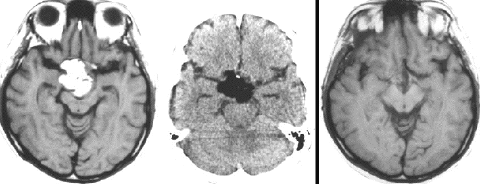

neurohypophyseal mixed germ cell tumorの若年成人男子例です。発症時のMRIでは大部分が増強されますが,腫瘍の右前方に脂肪組織を示す小さな信号域を認めます(上段左の単純MRI,上段右の増強MRI)。経蝶形骨洞生検術でmature teratomaとgerminomaの所見が得られました。ICE化学療法により増強される部分の腫瘍は消失しましたが,逆に下段左の単純MRIと下段中央のCTで認められる脂肪組織を含む部分が顕著に増大しました。この腫瘍は後に亜全摘出しました(下段右)が,病理所見は類皮腫でした。teratomaにおいてはこのような奇異な治療反応性 paradoxical response がみられることがあります。